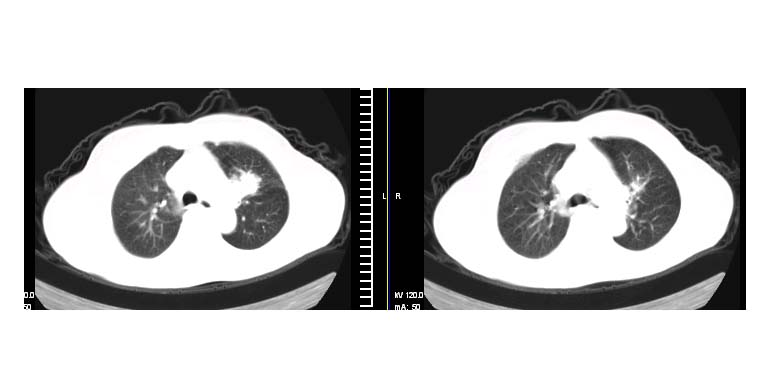

标题: CT11087:男性,82.咳嗽一周.抗炎治疗4-5天效果不明 [打印本页]

标题: CT11087:男性,82.咳嗽一周.抗炎治疗4-5天效果不明

左上肺实质性肿块,浅分叶 毛糙 胸膜凹陷征 纵隔淋巴结肿大——支持:左肺上叶周围型肺癌!

考虑左上肺癌(病灶有分叶,毛刺)可能性大.

考虑左上周围型肺癌伴左肺门淋巴结转移.

考虑左上肺周围性肺癌。